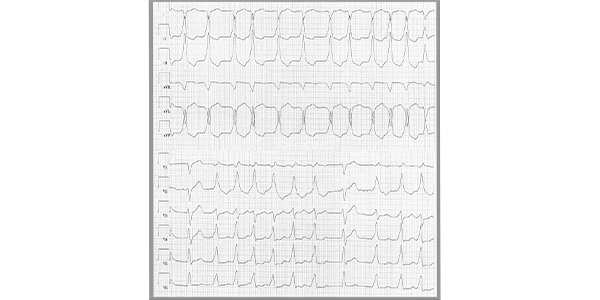

Everyday I see cases posted that are true learning pearls! we would love to showcase them at My ESc News. Please send them to 👉app.smartsheet.com/b/form/d11d100… we will do the magic 😍 @charles_driving @escardio @alexsfelixecho @echo_batman @echo_stepbystep @reirosbachiller @LopezOpitz